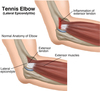

Your client has been diagnosed with

Tennis Elbow - Lateral Epicondylitis

Describe the region involved and position the client for work in this area.

- Forearm, elbow

- Supine

Your client has been diagnosed with

Tennis Elbow - Extensor Tendonitis

Describe the region involved and position the client for work in this area.

- Forearm, elbow

- Supine

- Describe: Tennis Elbow - Lateral Epicondylitis and Extensor Tendonitis

- Explain your treatment goals for the condition.

- Name 4 musculoskeletal structures involved in the condition

- Extensor Tenodinitis is inflammation or strain 1-2” distal to epicondyle at the musculotendinous junction of the extensors. Feel it when EXT wrist

- Lateral Epicondylitis is inflammation or pain at the L epicondyle with tenoperiosteal tearing (FX towards, never away)

- Tight wrist and finger extensor bellies transmit traumatic forces to origin of muscle

- Perpetuated by chronic extensor tension, repetitive stress, or traumatic reinjury

- Aggravated by forceful supination or wrist extension, especailly with pronation

- Mimicked by radiocapitellar joint injury

- Golfer’s elbow (medial epicondylitis) is a similar affliction of the medial elbow

GOALS:

1) >circ, decrease HT/spasm, decrease pain

2) breakdown and decrease ADH, fascial thickening, contracture, and excess scar tissue

- Increase tissue organization and integrity (facilitating functional tissue alignment with XXF and eccentric contraction)

3) >ROM

MUSCLES:

(Work pronators and FLX first before weak EXT)

- Biceps Brachii

- Brachioradialis

- Pronator Teres

- Wrist extensors / Common extensor tendon

- Name 4 musculoskeletal structures involved in Tennis Elbow - Lateral Epicondylitis and External Tendonitis

- Outline and highlight fiber alignment

- Demonstrate treatment for each strucure

- Name 2 potential endangerment sites at risk

-

Biceps Brachii (SH: Coracoid process, LH: Supraglenoid tubercle –> Tuberosity of radius and aponeurosis of biceps brachii)

-Arm is supinated by side, compression down bicep, petrissage -

Brachioradialis (Distal L 2/3 humerus –>styloid process radius)

-Muscle squeeze, petrissage -

Pronator Teres (common FLX tendon M epicondyle + coronoid process ulna –> middle of L radius)

-Sit behind client next to head, arm = 90 stop sign ABD from body. Squeeze PT at RC joint as they active pronate/supinate. Pin it, then stretch my extending and supinate forearm ABD from body - Wrist extensors / Common extensor tendon (1-2” distal from L epicondyle)

- -Compression while EXT of wrist

————-

ENDANGERMENT SITES:

- Antecubital Region

- Ulnar Notch